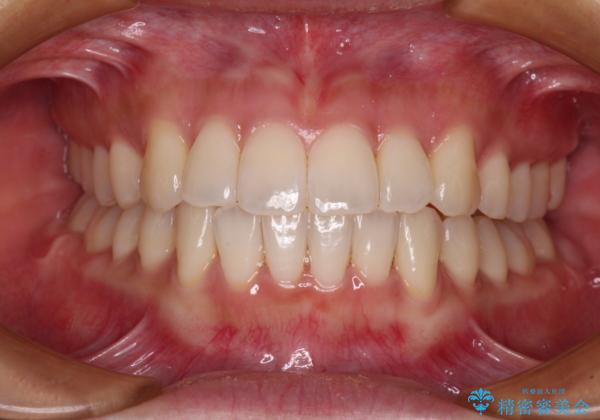

日々前歯の捻れが解消されていくので、歯の動きを楽しみながら矯正治療を進めることができました。

- 1年6ヶ月

- クリアブラケット